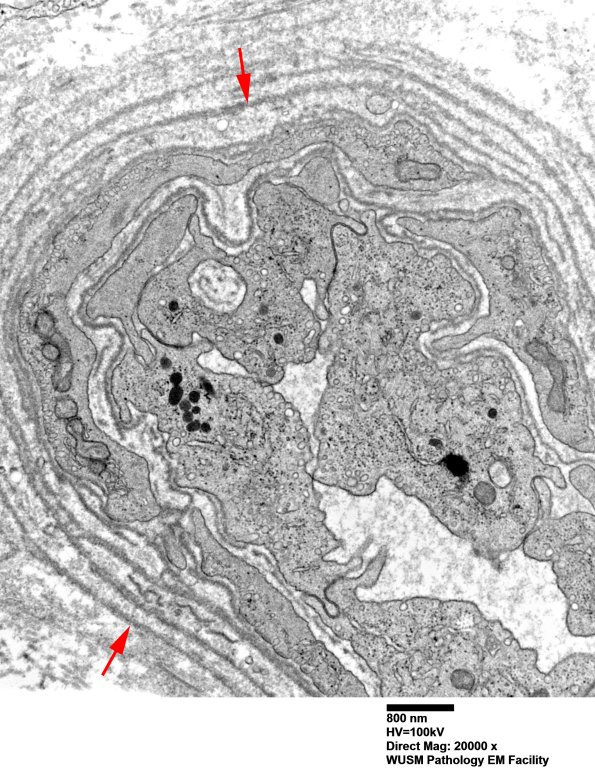

Accumulated mostly intact basal membranes (arrows, 16B2) expand the vessel wall. (electron micrographs)